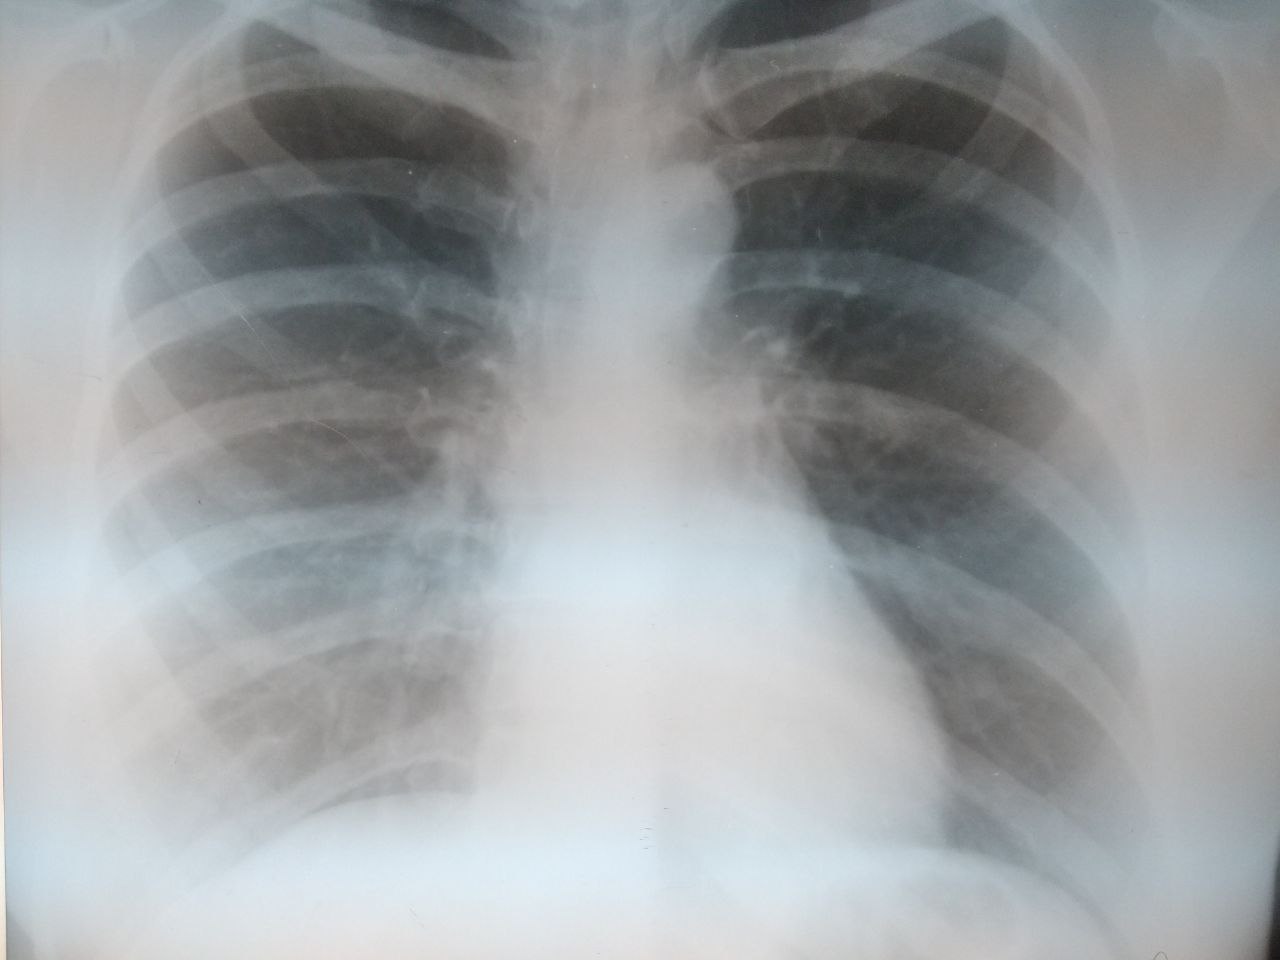

Добрый день, подскажите пожалуйста, есть ли инфильтрация? Или такой рисунок? Женщина, 1957 гр, жалобы на одышку в течение месяца, кашля и температуры нет

Очаговых и инфильтративных теней не определяется.